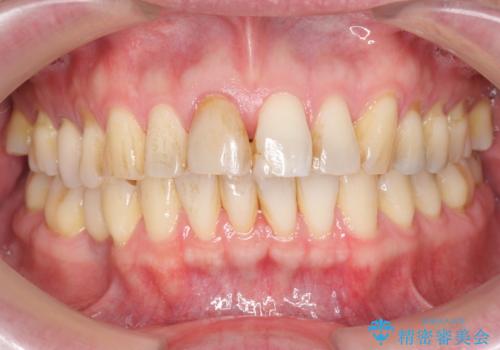

前歯の変色を改善 オールセラミック治療

感染の疑われる根管内に対し再度根管治療を行い、セラミッククラウンを作製することで審美性の回復します。

- 13.2万円(ジルコニアクラウン・仮歯)費用は治療当時の料金となります

目立つ前歯の審美性が改善したことで見た目を気にせず笑えるようになった。との嬉しい感想をいただくことができました。